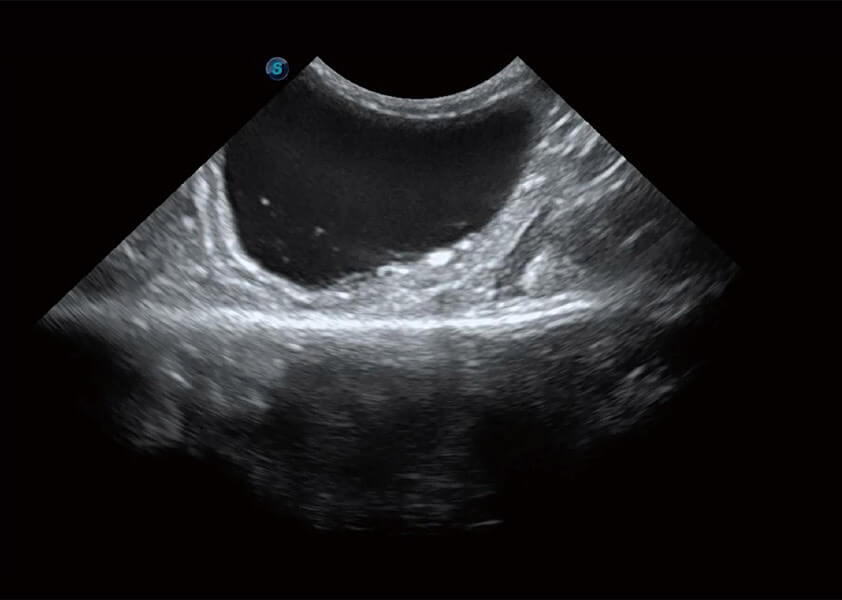

ProPet 60 作为一款高端台式动物超声设备,为动物医生的日常诊断提供了一系列贴合动物临床需求、解决临床实际问题的高级成像功能。凭借全系列高清探头,满足医生对腹部、心脏、生殖、浅表、肌骨等成像的所有需求,切实帮助您提升检查效率,提高诊断信心。

动物是人类最亲密的朋友和最值得信赖的伙伴。竞技宝(JJB)官方网站也一直致力于探索动物专用的超声影像解决方案。 全新推出的ProPet系列,是竞技宝(JJB)官方网站在动物超声影像智能化、专业化、精准化的一次跨越式革新。动物不能用言语来表述自己的不适,通过超声影像,ProPet系列搭建了动物医生与不同物种沟通的“桥梁”,为动物医生注入了“治愈之力”。